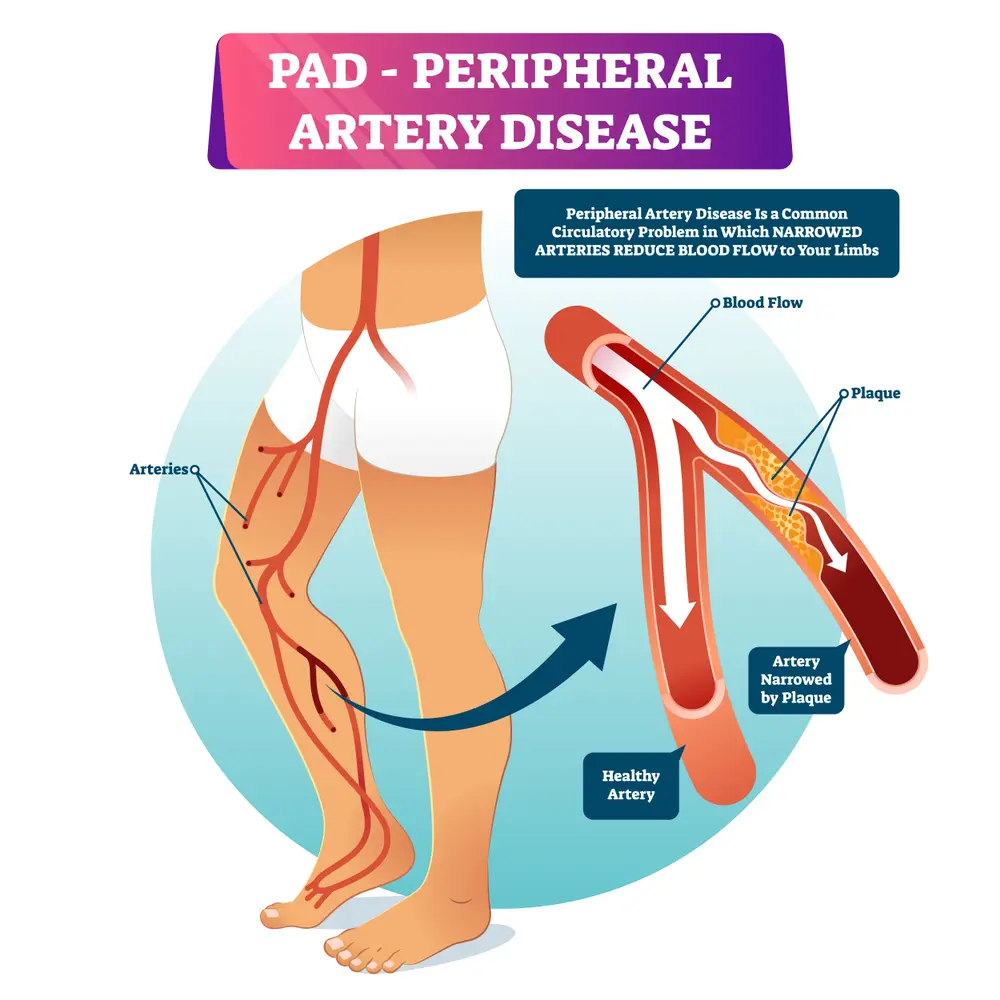

- Peripheral Vascular Disease • Georgetown • Naturopath • Natural Health Clinic of Halton (March 19, 2017)

- Poor Blood Circulation, Peripheral Artery Disease • Georgetown • Acupuncture • Natural Health Clinic of Halton (March 6, 2022)